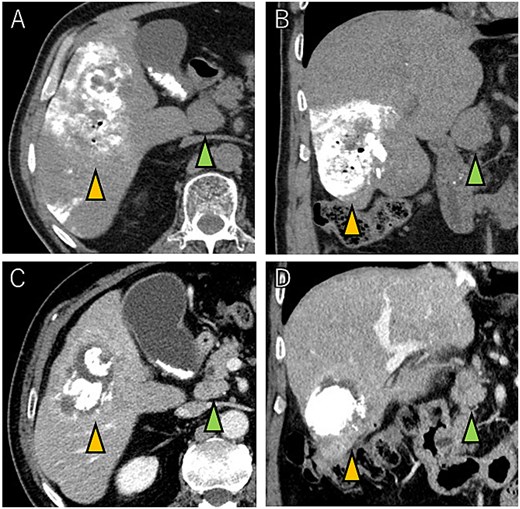

A 72-year-old man presented with abdominal pain. Computed tomography (CT) revealed a liver tumor in segment six/five, abutting the transverse colon without invading. Enlarged lymph nodes in regions 12b and 16b1 were noted, but there were no lung metastases or ascites. Magnetic resonance imaging revealed multiple nodular lesions in liver S6/5 with low signal intensity on T1-weighted images, and mosaic-like high signal intensity on T2-weighted images (Fig. 1). Based on these findings, the diagnosis of HCC was made, staged as cT2N1M1 Stage IVB. The patient underwent transarterial chemoembolization (TACE) followed by ATZ + BV therapy, resulting in tumor and lymph nodes reduction (Fig. 2).

Tumor and enlarged lymph node in region 12b before ATZ + BV (A and B), and which got reduction after chemotherapy (C and D).

CT images showing tumor and enlarged lymph nodes in region 12b before ATZ + BV therapy (A and B). After chemotherapy, reduction of the tumor and lymph nodes is evident (C and D). Notably, no abscess formation was observed in the HCC or surrounding liver tissue, highlighting the direct communication between the tumor and the colon.